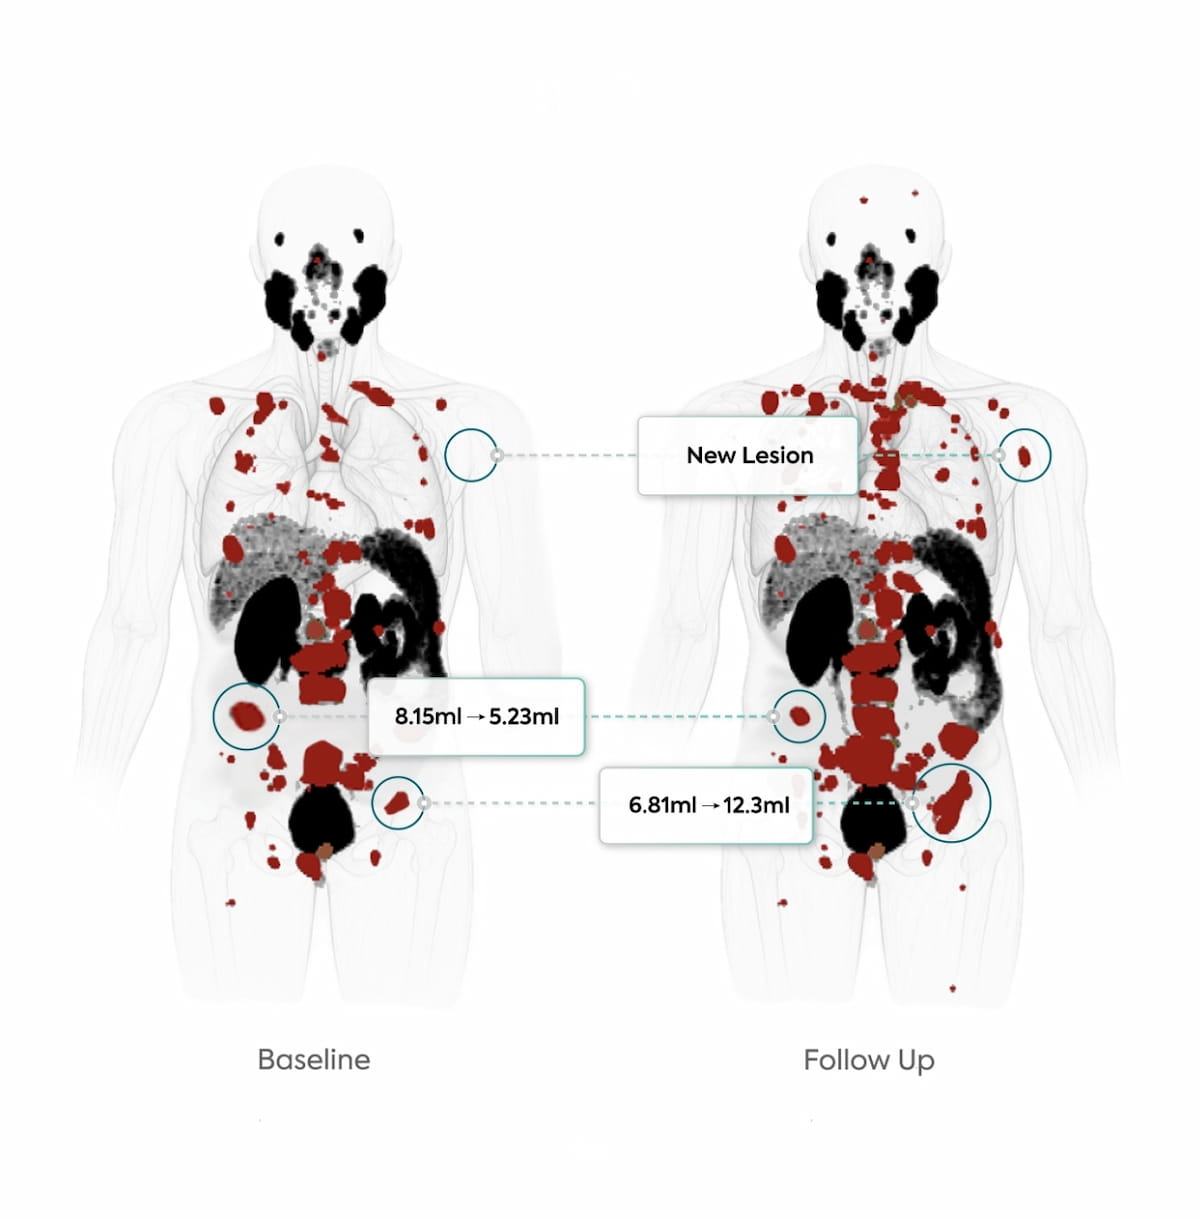

The iPETcertum software reportedly provides automated segmentation and enhanced visualization of regions of interest on PET scans with a single click.